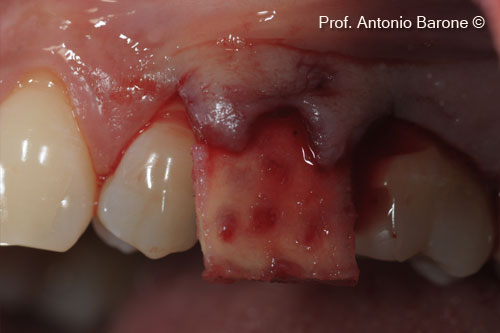

Hình ảnh lâm sàng của một ổ răng mới bị mất hoàn toàn xương nền má

Hình ảnh lâm sàng mặt ngoài của ma trận Derma được cấy ghép vào mặt ngoài bằng vạt bao